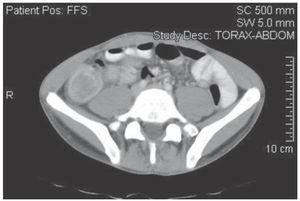

A 32 year old male was admitted to the emergency room with sudden-onset, crampy abdominal pain, nausea, and vomiting lasting for 10 hours. He had presented with similar symptoms in the past. On physical examination the abdomen was distended, tender and a four centimeters olive-like mass was palpated in the right lower quadrant. Abdominal X-ray showed nonspecific dilation of small-bowel loops. An abdominal tomography was performed and a target sign image was found in proximity to the ileocecal area (Figure 1). A colonoscopy showed a large mass protruding into the cecum through the ileocecal valve (Figure 2). Colonoscopic and tomographic findings were consistent with the diagnosis of ileocolic intussusception and the patient was taken to the operating room for an emergent laparotomy. Intraoperative findings included dilated small bowel and an ileocolic intussusception. The intussusception was not reduced and a right hemicolectomy with stapled ileocolostomy was performed (Figure 3). Pathological examination was consistent with Hodgkin's lymphoma-scleronodular type as the cause of ileocolic intussusception (Figure 4). The patient received postoperative chemotherapy for six months (cyclophosphamide, doxorubicin, vincristine, and prednisone). At seven years follow-up the patient is asymptomatic without evidence of tumor activity and with normal gastrointestinal function.

¿ Figure 1. Contrast enhanced CT scans demonstrated an ileocolic intussusception.